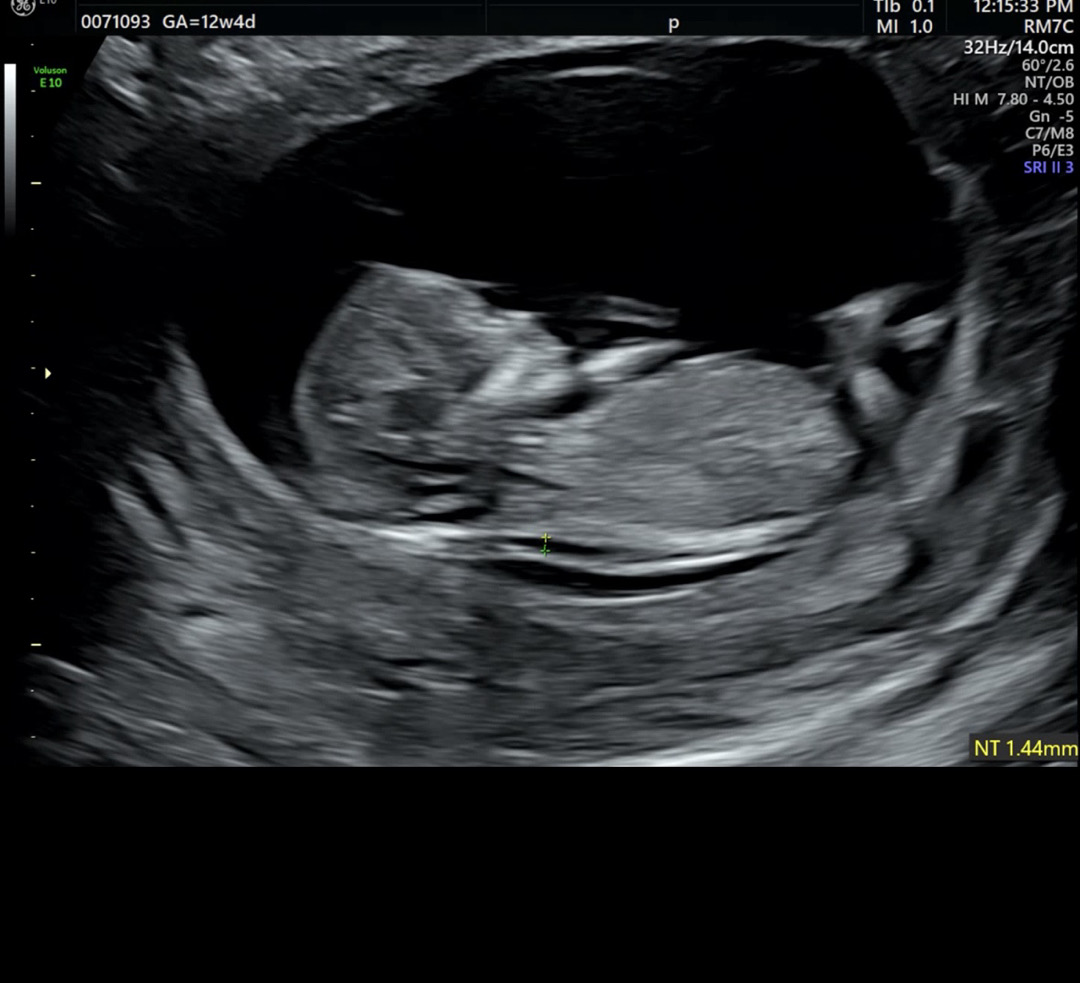

12주4일 챗지피티는 딸일거 같다는데..

오늘 1차 기형아 검사하고 왔어요 !! 딸일까요 아들일까요 너무 궁금해요 각도법 봐주세요 ><